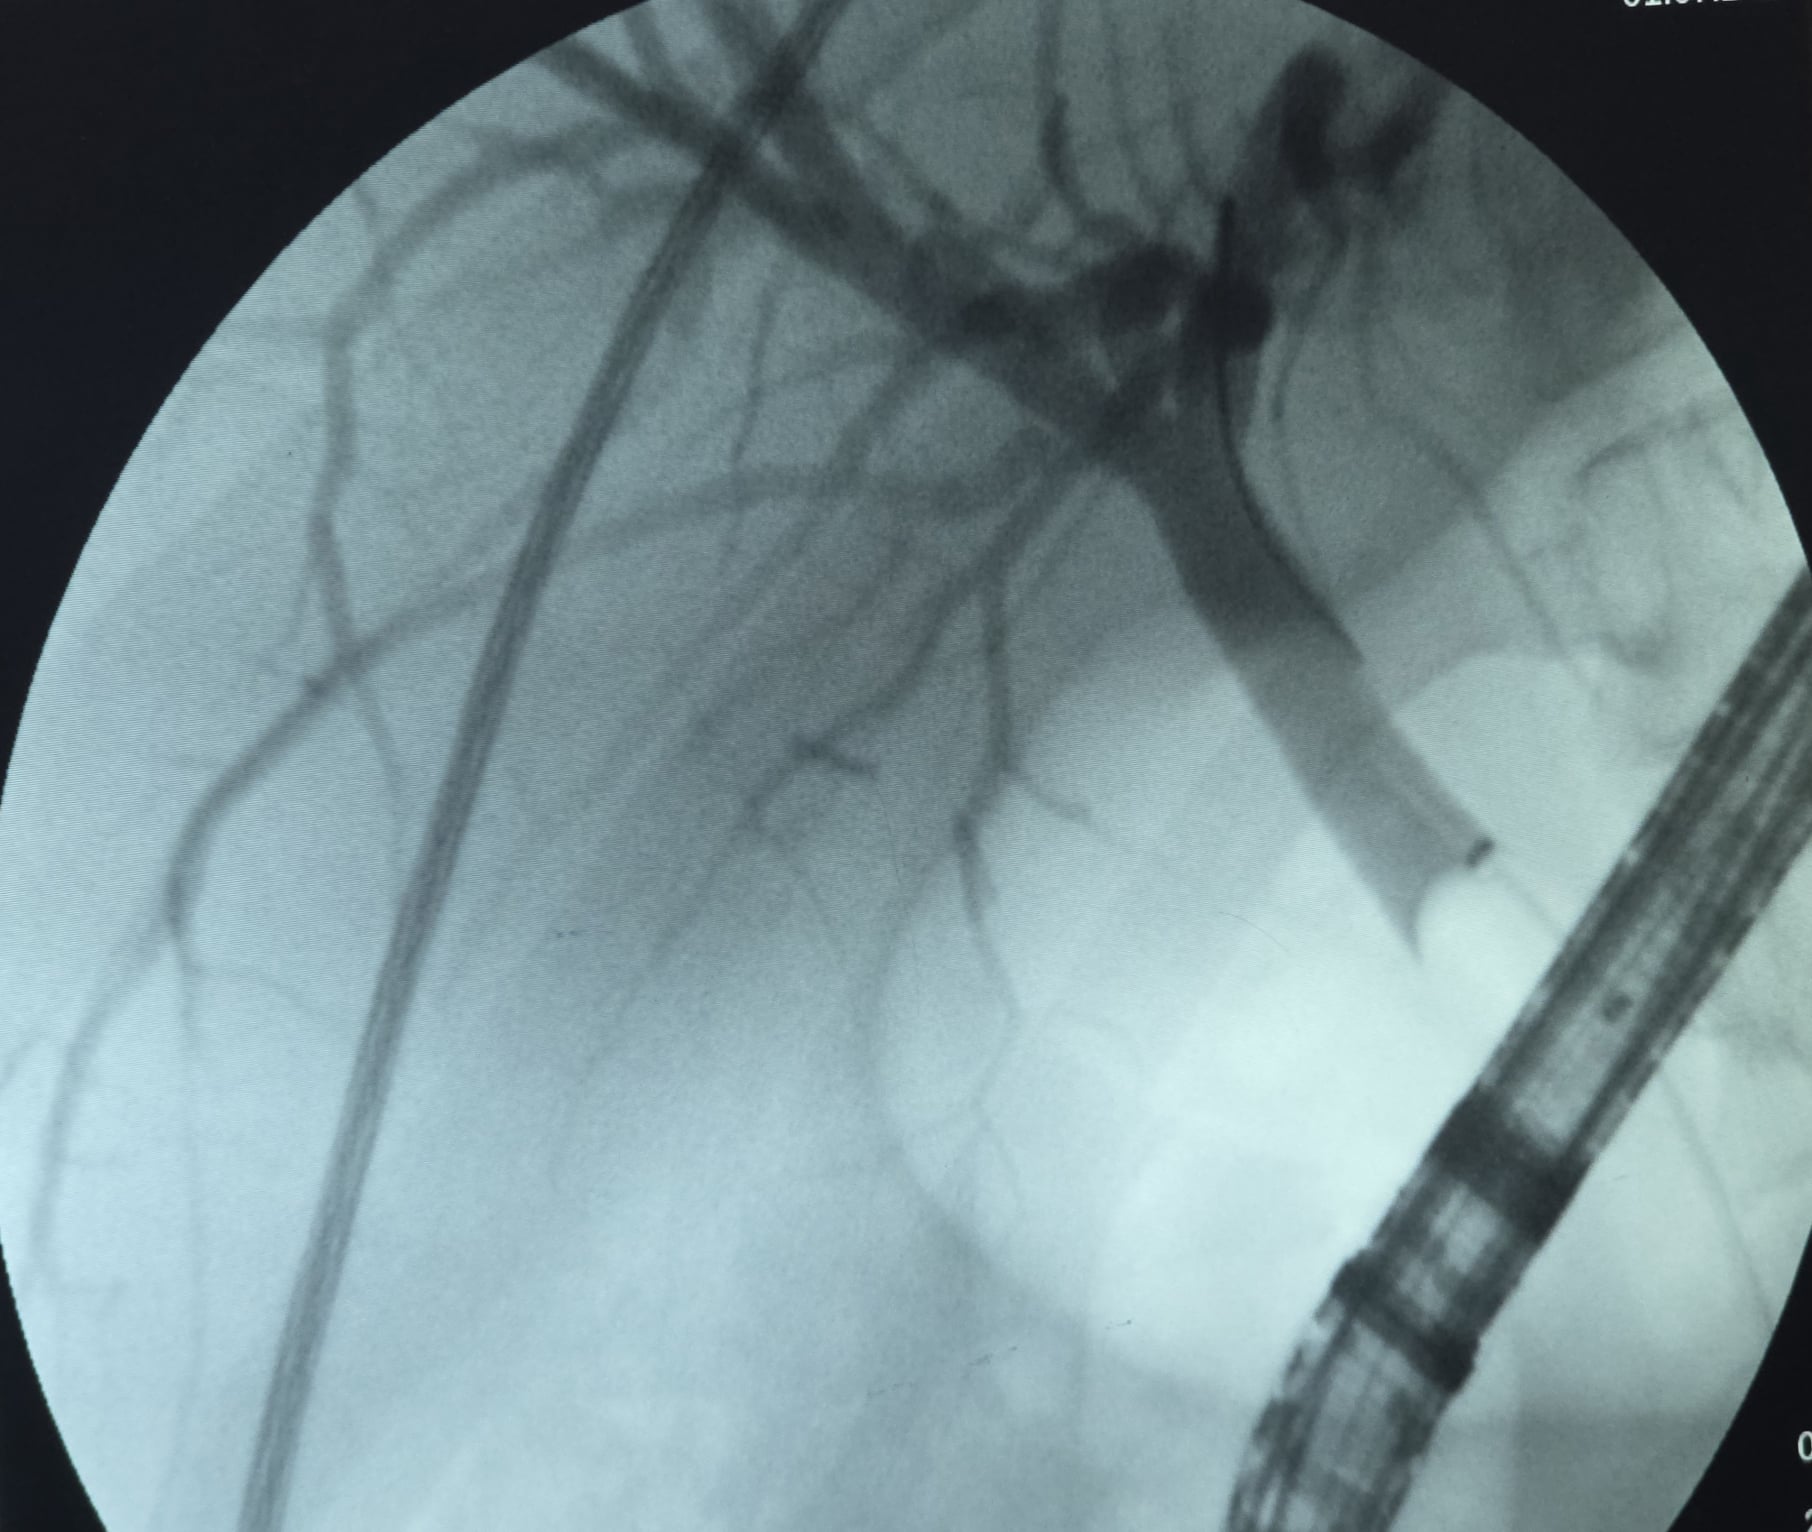

Normal kolanjiyografi

Koledokta dolum defektleri